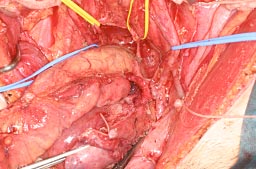

• S状結腸・直腸合併子宮・両側付属器切除術. 結腸と直腸を手縫いにて端々吻合.